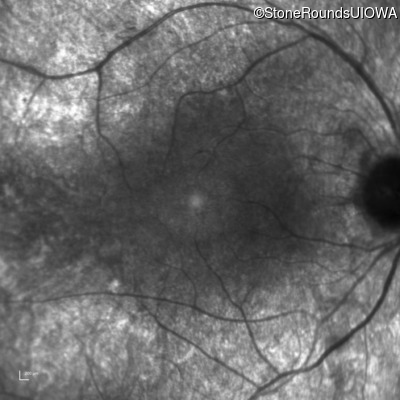

Type 2 Usher Syndrome (IB1b)

Age at visit:

33 years

OD

OS

20/40

20/32 -2

Diagnosis & molecular findings

Disease

Gene

Allele 1 variant(s)

Allele 2 variant(s)

Inheritance mode

Type 2 Usher Syndrome

USH2A

Cys536Arg TGC>CGC

Trp3521Arg TGG>CGG

AR